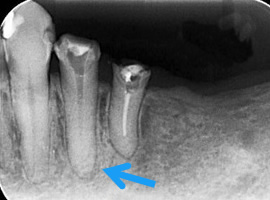

歯根端切除術(重度の虫歯)

適切な根管治療を行っても、痛みが取れなかったり、根尖病変が治らなかったりする場合もあります。

その時は、歯肉を切開して病変部に直接アプローチし、中を掃除いたします。